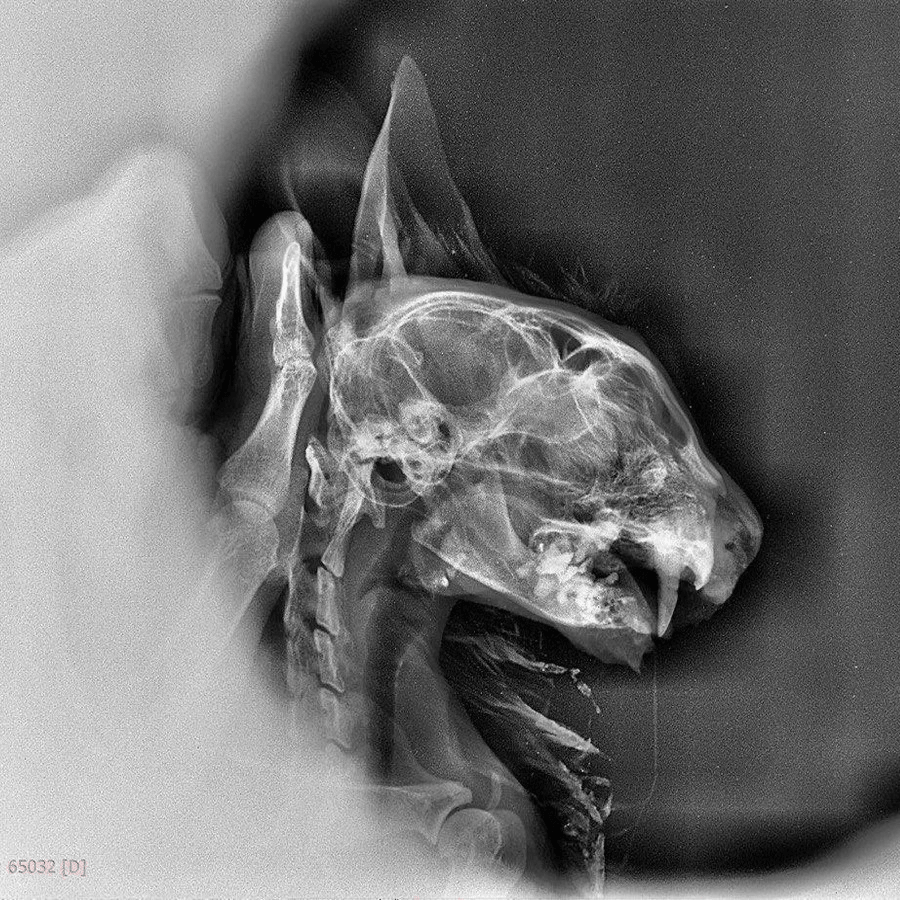

Марийка: черепно-мозговая травма и перелом челюсти

В двадцатых числах февраля 2026 года в Москву прилетела эта кошечка, и мы начали очередную борьбу за жизнь. У кошки черепно-мозговая травма и перелом челюсти. Ни есть, ни пить она не может. Подбросили кошку к местному веткабинету неизвестные люди в Дербенте, и там, конечно, кошке ничем помочь не смогли. Что случилось с беднягой - мы уже не узнаем. Назвали мы ее Марийкой.

На 10.04.2026 Прогнозы остаются осторожными. Состояние тяжелое, нестабильное. Активность сильно снижена, лежащую физиологичную позу может удерживать 15-20 сек, затем снова ложится в боковое положение тела, наклон головы влево сохраняется. При пробном кормлении через рот -глотает хорошо. Но кормят по прежмену через стому.. Температура поддерживается на грелке. Давление в пределах нормы, но на поддержании препаратами. По ока лейкоциты 21,4, эритроциты 5, гематокрит 24,1%, тромбоциты 135. 3% атипичных клеток.По бх креатинин 191, мочевина 18,8, билирубин 37,7, альбумин 21. Откорректировали терапию на основании анализов. Лейкемия пцр ДНК отрицательно. ИФА в работе. У Марийки диагнозы из инфекций: калицивироз, ринотрахеит, иммунодефицит, гемобартонеллез. Множественные переломы костей черепа, перелом челюсти. Чмт.Холангиогепатит, гепатопатия.

Состояние у кошечки стабильно тяжелое. Активность сегодня умеренная, просит ласки. Аппетит есть, кушает сама немного и так же докармливают через стому. Марийка сейчас может скушать около 1/4 от нормы, но потом она устаёт. Рот закрыть до конца она так и не может, разрабатывать сустав явно придется дольше, чем мы думали.

Точного неврологического диагноза у неё на данный момент нет. Консультация невролога не лишняя, но Марийка не в том состоянии, чтобы адекватно перенести перевозку (она на грелке и на препаратах для поддержания давления).